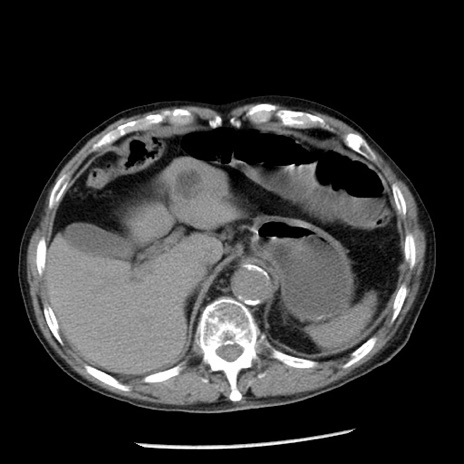

症例26(横断像)

【症例】80歳代男性

【主訴】嘔吐

【現病歴】昨晩2回嘔吐あり、今朝になっても嘔吐あり。来院。

【既往歴】胃潰瘍

【身体所見】意識清明、BT 37.6℃、BP 166/95mmHg、HR 100bpm、SpO2 97%、腹部:平坦・軟、腸蠕動音聴取良好、圧痛なし。

【データ】WBC 21900、CRP 1.46